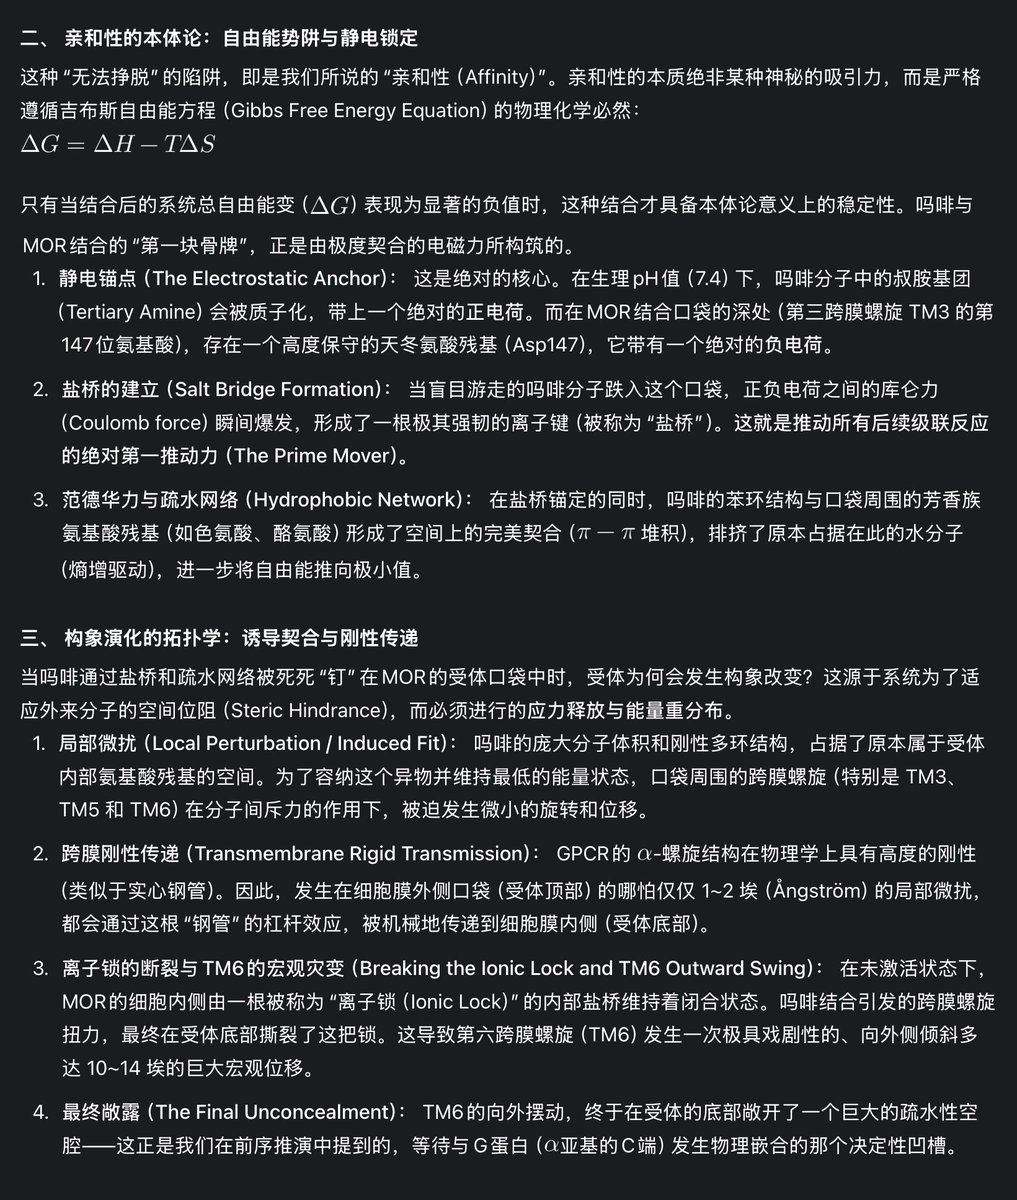

关于后藤提到过的“反解离”

首先,从定义上讲,“反解离(anti-dissociative)”并不是一个标准的医学术语或者广泛认同的药理学分类。在正规资料,比如医学文献、维基百科、精神药理学教科书中,目前并没有“反解离药物”这个正式概念。

看上去像是为了描述某类特定效应而创造的术语(可能是nmda受体活性增强),用来对抗因NMDA受体拮抗剂(比如氯胺酮、DXM、PCP等)引发的解离体验(dissociation)。

那么更常见的是将其归入认知增强剂(cognitive enhancers),特别是改善认知连接性(connectivity)和现实感知(reality testing)的类型。

但其实在药理学上,单纯用“受体激动剂”来逆转“受体拮抗剂”的效应,有时会导致过度激活。

对于NMDA受体而言,过强的NMDA活化本身就与兴奋性毒性(excitotoxicity)和精神病样症状(psychotomimetic effects)有关,比如谷氨酸风暴可以引发严重的焦虑、妄想、乃至癫痫。

也就是说,简单地“激动-解除拮抗”在中枢神经系统是很危险的做法,尤其是对于易感个体(如有精神分裂素质的人)。

科学的处理方式一般是通过更细致的调节,比如微调NMDA/AMPA平衡、调节其他辅助途径(如GABA、5-HT、mGluR受体),而不是简单粗暴地用“NMDA增强剂”去顶回去。

而临床处理药物中毒中,其实医生更常用的做法是保守、支持性的治疗,比如补液,促进代谢,必要时镇静,以及监测生命体征防治并发症。

药物拮抗与受体激动之间,往往牵扯到的是复杂的适应性变化(receptor upregulation/downregulation),

不是简单的“给多一点刺激就能抵消”的关系